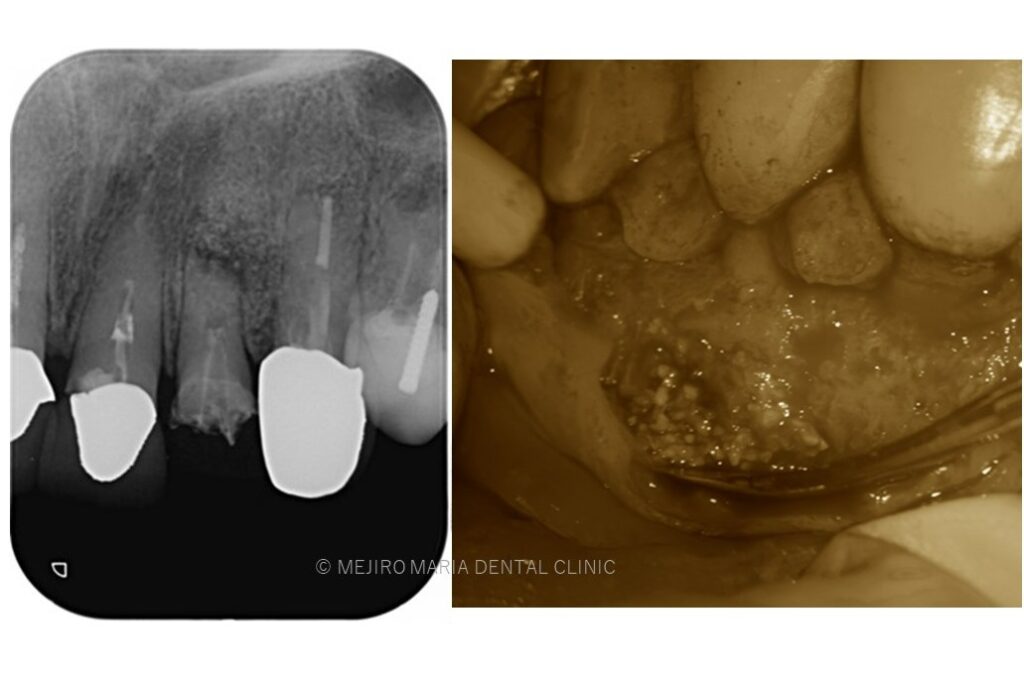

でのリカバリー_該当歯牙の精密根管治療後のレントゲン画像.jpg)

でのリカバリー_感染した人工骨の画像.jpg)

今回の症例は、他院にて歯根端切除術を行った根尖部(歯の根の先)に充填された人工骨の感染が原因と考えられます。

歯根端切除術後は術後の透過像で治癒を確認することが重要であり、感染が除去できていれば骨は患者自身の力で自然に再生を行うことになるので、人工骨を充填することはリスクが高い行為であると考えます。